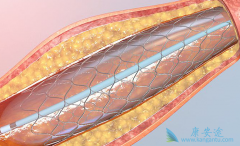

为了改善冠心病介入治疗短期和长期的疗效与安全性,所以研发了支架。第一代支架是金属裸支架,使冠心病介入治疗前进了一大步,使介入治疗变得非常安全,当血管发生严重狭窄时单纯球囊扩张预处理后,再用支架把血管完全撑开,就能解除心肌缺血危险,而且 ...

心脏支架 选哪种?放最好的支架?还是放最贵的支架?今天就给大家答疑解惑!心脏支架由具有强支撑力的合金制成,不同厂家支架的金属结构略有差别。心脏支架没有植入体内之前,包裹在球囊外面。植入时给球囊加压,支架打开至预定直径,使支架与血管壁完 ...

心脏支架作为现代心血管医学发展中的一个里程碑,确实在冠心病的治疗中发挥着非常重要的价值。 生物可降解支架 给冠心病介入治疗带来了新的革命。但是生物可降解支架真的能成为心血管患者的福音吗?目前心脏支架主要分为不可降解支架和完全降解支架两个 ...

生物可降解支架 安全吗?其实早在20世纪90年代初,就已经提出生物可降解支架的概念,但发展没有金属裸支架和药物洗脱支架快,最终被药物洗脱支架所替代。目前药物洗脱支架长期随访发现潜在的支架内血栓风险,最近10余年生物可降解支架科技和材料学取得 ...